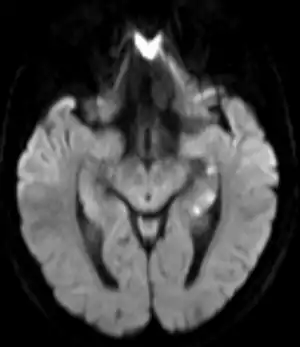

| Transiente globale Amnesie MRT DWI axial | |